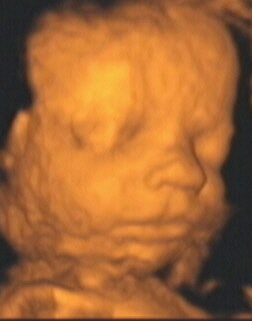

![]() |

| Figure 12, a 3-D ultrasound image of a fetal mouth and nose at 32 weeks gestation. Image courtesy of Stefano Ciatti, M.D. |